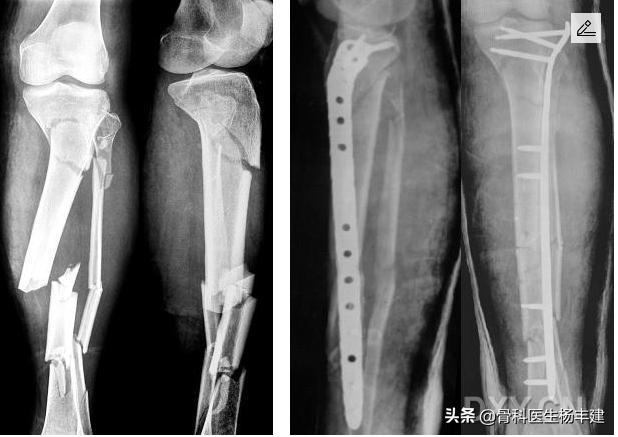

骨折断端萎缩,间隙增大,典型的“骨折不愈合”表现

发生延迟愈合或者不愈合,骨折处持续发生微动,应力持续作用于跨越骨折线的“钢板”等上,就会造成“钢板”疲劳。一旦疲劳程度超过钢板设计的上限,就会发生“钢板”断裂。好比一辆汽车的设计使用寿命是10年,那么一直使用到15年的时候,随时发生抛锚事件就不足为怪了。

(2)钢板原理使用不当

根据骨折的不同形式,钢板的固定原理分为“加压固定”“桥接固定”“支撑固定”等等多种固定原理。对于长骨的粉碎性骨折,使用钢板时一定注意桥接固定原理原理,这种情况下螺丝钉的安排非常讲究。我们注意到,有些基层的医生在这一方面略微欠缺,有时候会做出不伦不类的固定来。充分理解这些原理,是骨科医生与木匠的区别。

桥接钢板往往用于复杂的粉碎性骨折,用好桥接板并不是简单事情